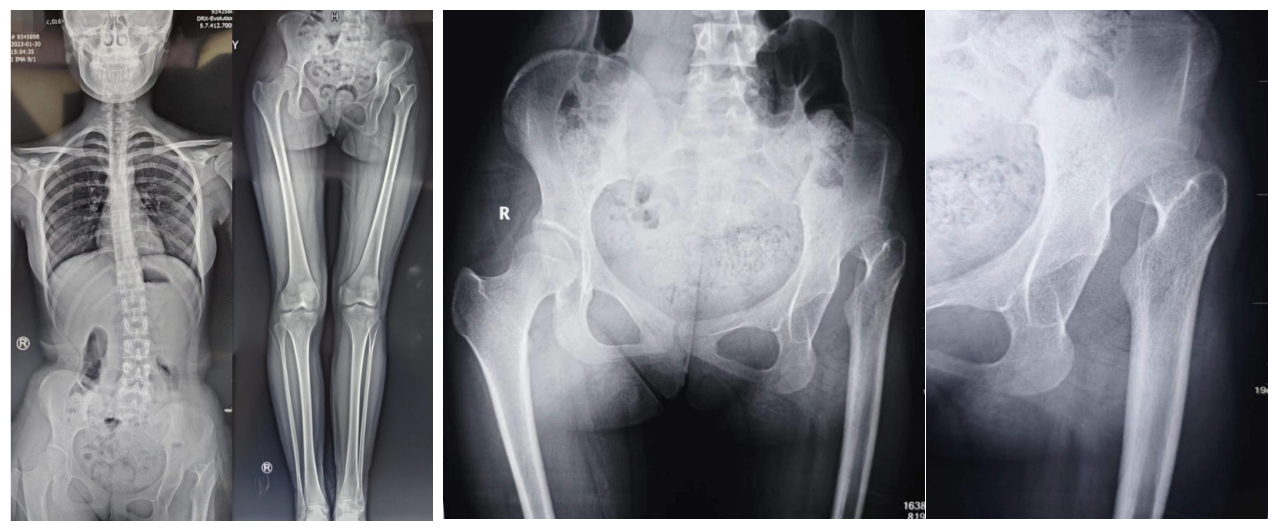

术前影像资料

患者女性,16岁,自学步以来就呈现跛行步态,近一年疼痛加剧,严重影响日常生活,遂来兰大二院就诊。入院后,骨科主任夏亚一教授结合患者病史及检查、检验结果,明确诊断为发育性髋关节发育不良(左侧完全脱位)。由于长期髋关节脱位导致双下肢不等长活动跛行,已造成继发骨盆倾斜及脊柱侧弯畸形,为保留自身关节并纠正脊柱侧弯畸形,经讨论评估后拟为患者实施改良髋关节复位髋关节囊成形术(Colonna手术)。手术由解放军总医院程徽教授和兰大二院骨科姚长江副主任医师共同完成,术中用时2.5个小时,术后出血量小,复查左股骨头已完全复位于人造髋臼内,目前临床疗效满意,可以达到推迟关节置换甚至避免置换的目的。